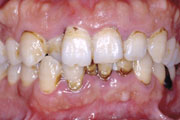

症例2

45歳女性です。奥歯のかぶせ物がはずれたため来院されました。歯肉の腫れが顕著ですし、

前歯の審美性も損なわれています。お口全体を精密に検査をし、綿密な計画を立てて、歯周病治療を行いながら、前歯、奥歯ともに審美的な修復治療をしました。